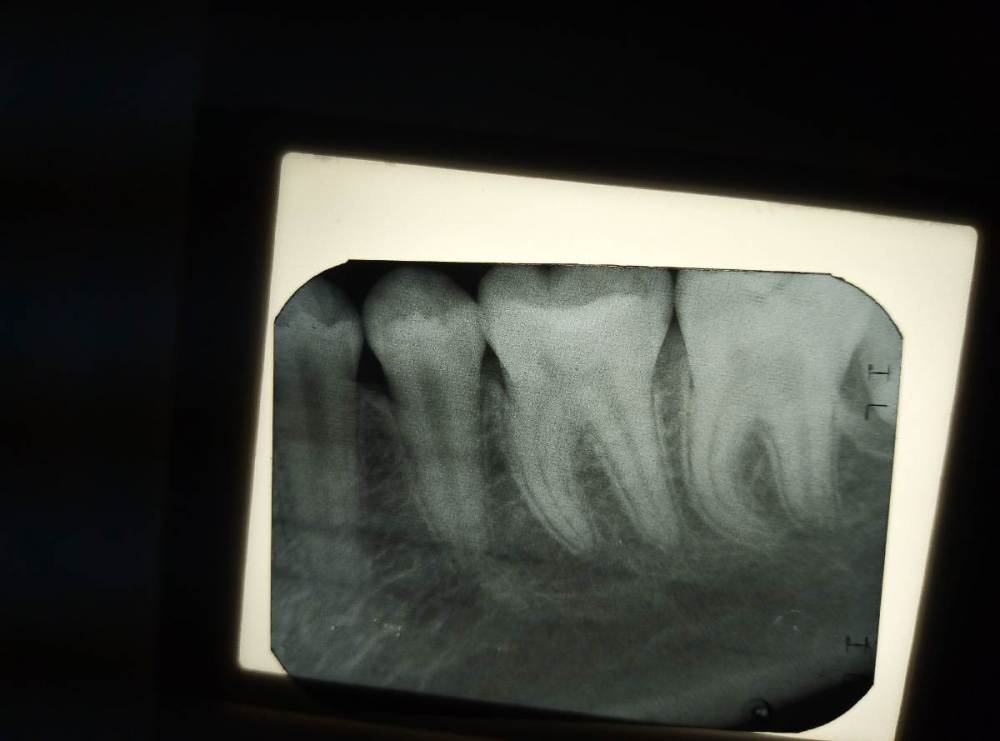

АВА2018 Опубликовано 10 ноября, 2021 Поделиться Опубликовано 10 ноября, 2021 Коллеги, прикрепляю снимок до лечения. Сегодня она не пришла, сказала, что зуб перестал болеть... Но всё возможно... Ссылка на комментарий

vse32 Опубликовано 10 ноября, 2021 Поделиться Опубликовано 10 ноября, 2021 10 минут назад, АВА2018 сказал: Коллеги, прикрепляю снимок до лечения. Сегодня она не пришла, сказала, что зуб перестал болеть... Но всё возможно... Теоретически, тут до пульпита, как до Луны. Ссылка на комментарий

АВА2018 Опубликовано 10 ноября, 2021 Поделиться Опубликовано 10 ноября, 2021 9 минут назад, vse32 сказал: Теоретически, тут до пульпита, как до Луны. Я вот думаю на фосфат-цемент.... СОГЛАСНА, что по снимку далеко до пульпы, но при снятии пломбы, ближе к медиальному рогу пульпы лежала прокладка из Сица. Насчёт анестетика я попробую, если разболится. Вообще работаю с детьми и есть тот страх по поводу анестезии Ссылка на комментарий